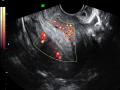

Tag: ultrassonografia transvaginal

Diagnóstico por imagem em ginecologia - Quinto ano medicina